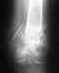

ладьевидная кость запястья (закрытый перелом со смещением)

В травме сказали: 1% что срастется само, без операции. И нужно или спицы ставить или винт Бергера. Если можно, подскажите пожалуйста, какой вариант предпочтительнее в моей ситуации, плюсы и минусы вариантов и ориентировочную стоимость операции для того и другого варианта(хотя бы порядок). А также есть ли смысл торопиться с операцией или благоразумнее подождать в надежде на этот 1%.

• Кликните для загрузки файла рентген.jpg

72KB (74218 bytes)